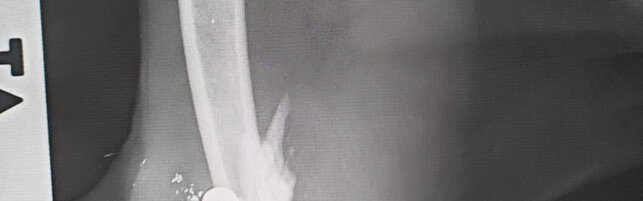

Arezzo, spari contro due gattine: corsa contro il tempo per salvarle

Violenza in una colonia felina nel Casentino, le due micie sono dai veterinari: "Stiamo cercando di alleviare il dolore"